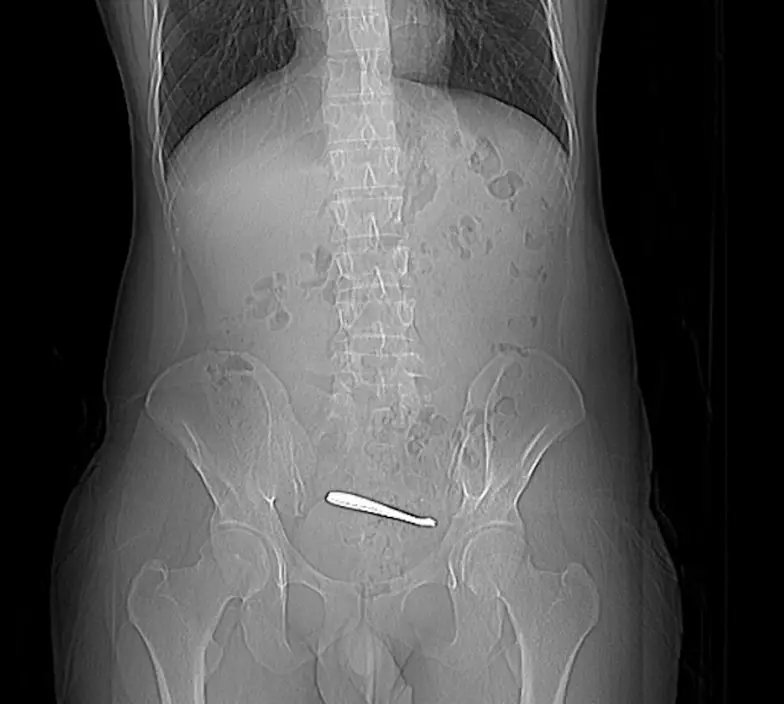

腹痛1周求診 CT揭腸道藏兩把匙羹

近日,陝西西安一名28歲張姓男子因持續腹痛一周前往求診,經電腦斷層掃描(CT)檢查後赫然發現腸道內竟藏有兩把匙羹。據南京鼓樓醫院消化內科介紹,張先生最初於西安接受檢查,CT顯示腸道內出現一條狀高密度影像。經追問病史,張先生才想起3周前曾誤吞匙羹,惟異物一直未能自然排出,最終引發腹痛不適。由於不希望接受外科手術,他經朋友介紹轉往南京鼓樓醫院求診。

匙羹卡回腸末端 黏膜潰瘍險釀穿孔

入院後,醫生為張先生再次安排CT及腸鏡檢查,確認兩把匙羹卡在回腸末端,周邊黏膜已出現潰瘍變化,隨時有腸道穿孔風險,情況相當危險。由於異物長約12CM,且位處腸腔較狹窄的小腸位置,取出難度甚高。醫療團隊經過近1小時的細緻操作,最終成功以內窺鏡將兩把匙羹完整取出,令患者免卻接受剖腹手術之苦。